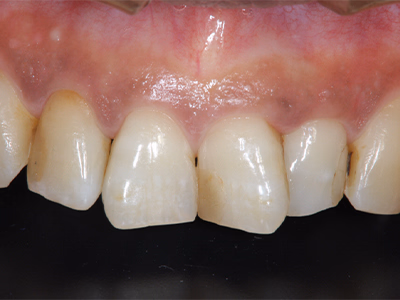

前歯のセラミックス

治療前後写真

治療前

治療後

年齢・性別

50歳・女性

来院理由

前歯の変色・審美障害

治療内容

全体ホワイトニング→失活歯(#11)を再根管治療→#11フルセラミックス修復

#21はレジン充填

治療期間

約3ヶ月

費用

- ホワイトニング 88,000円

- 感染根管治療 121,000円

- セラミック 170,500円

- コンポジットレジン 33,000円

リスク・副作用

歯肉退縮で境目が見える可能性

過度な咬合力でセラミックのチッピング

医院コメント

生物学的安定性を確保した上でセラミックを接着し、色・透明感を自然に調和。